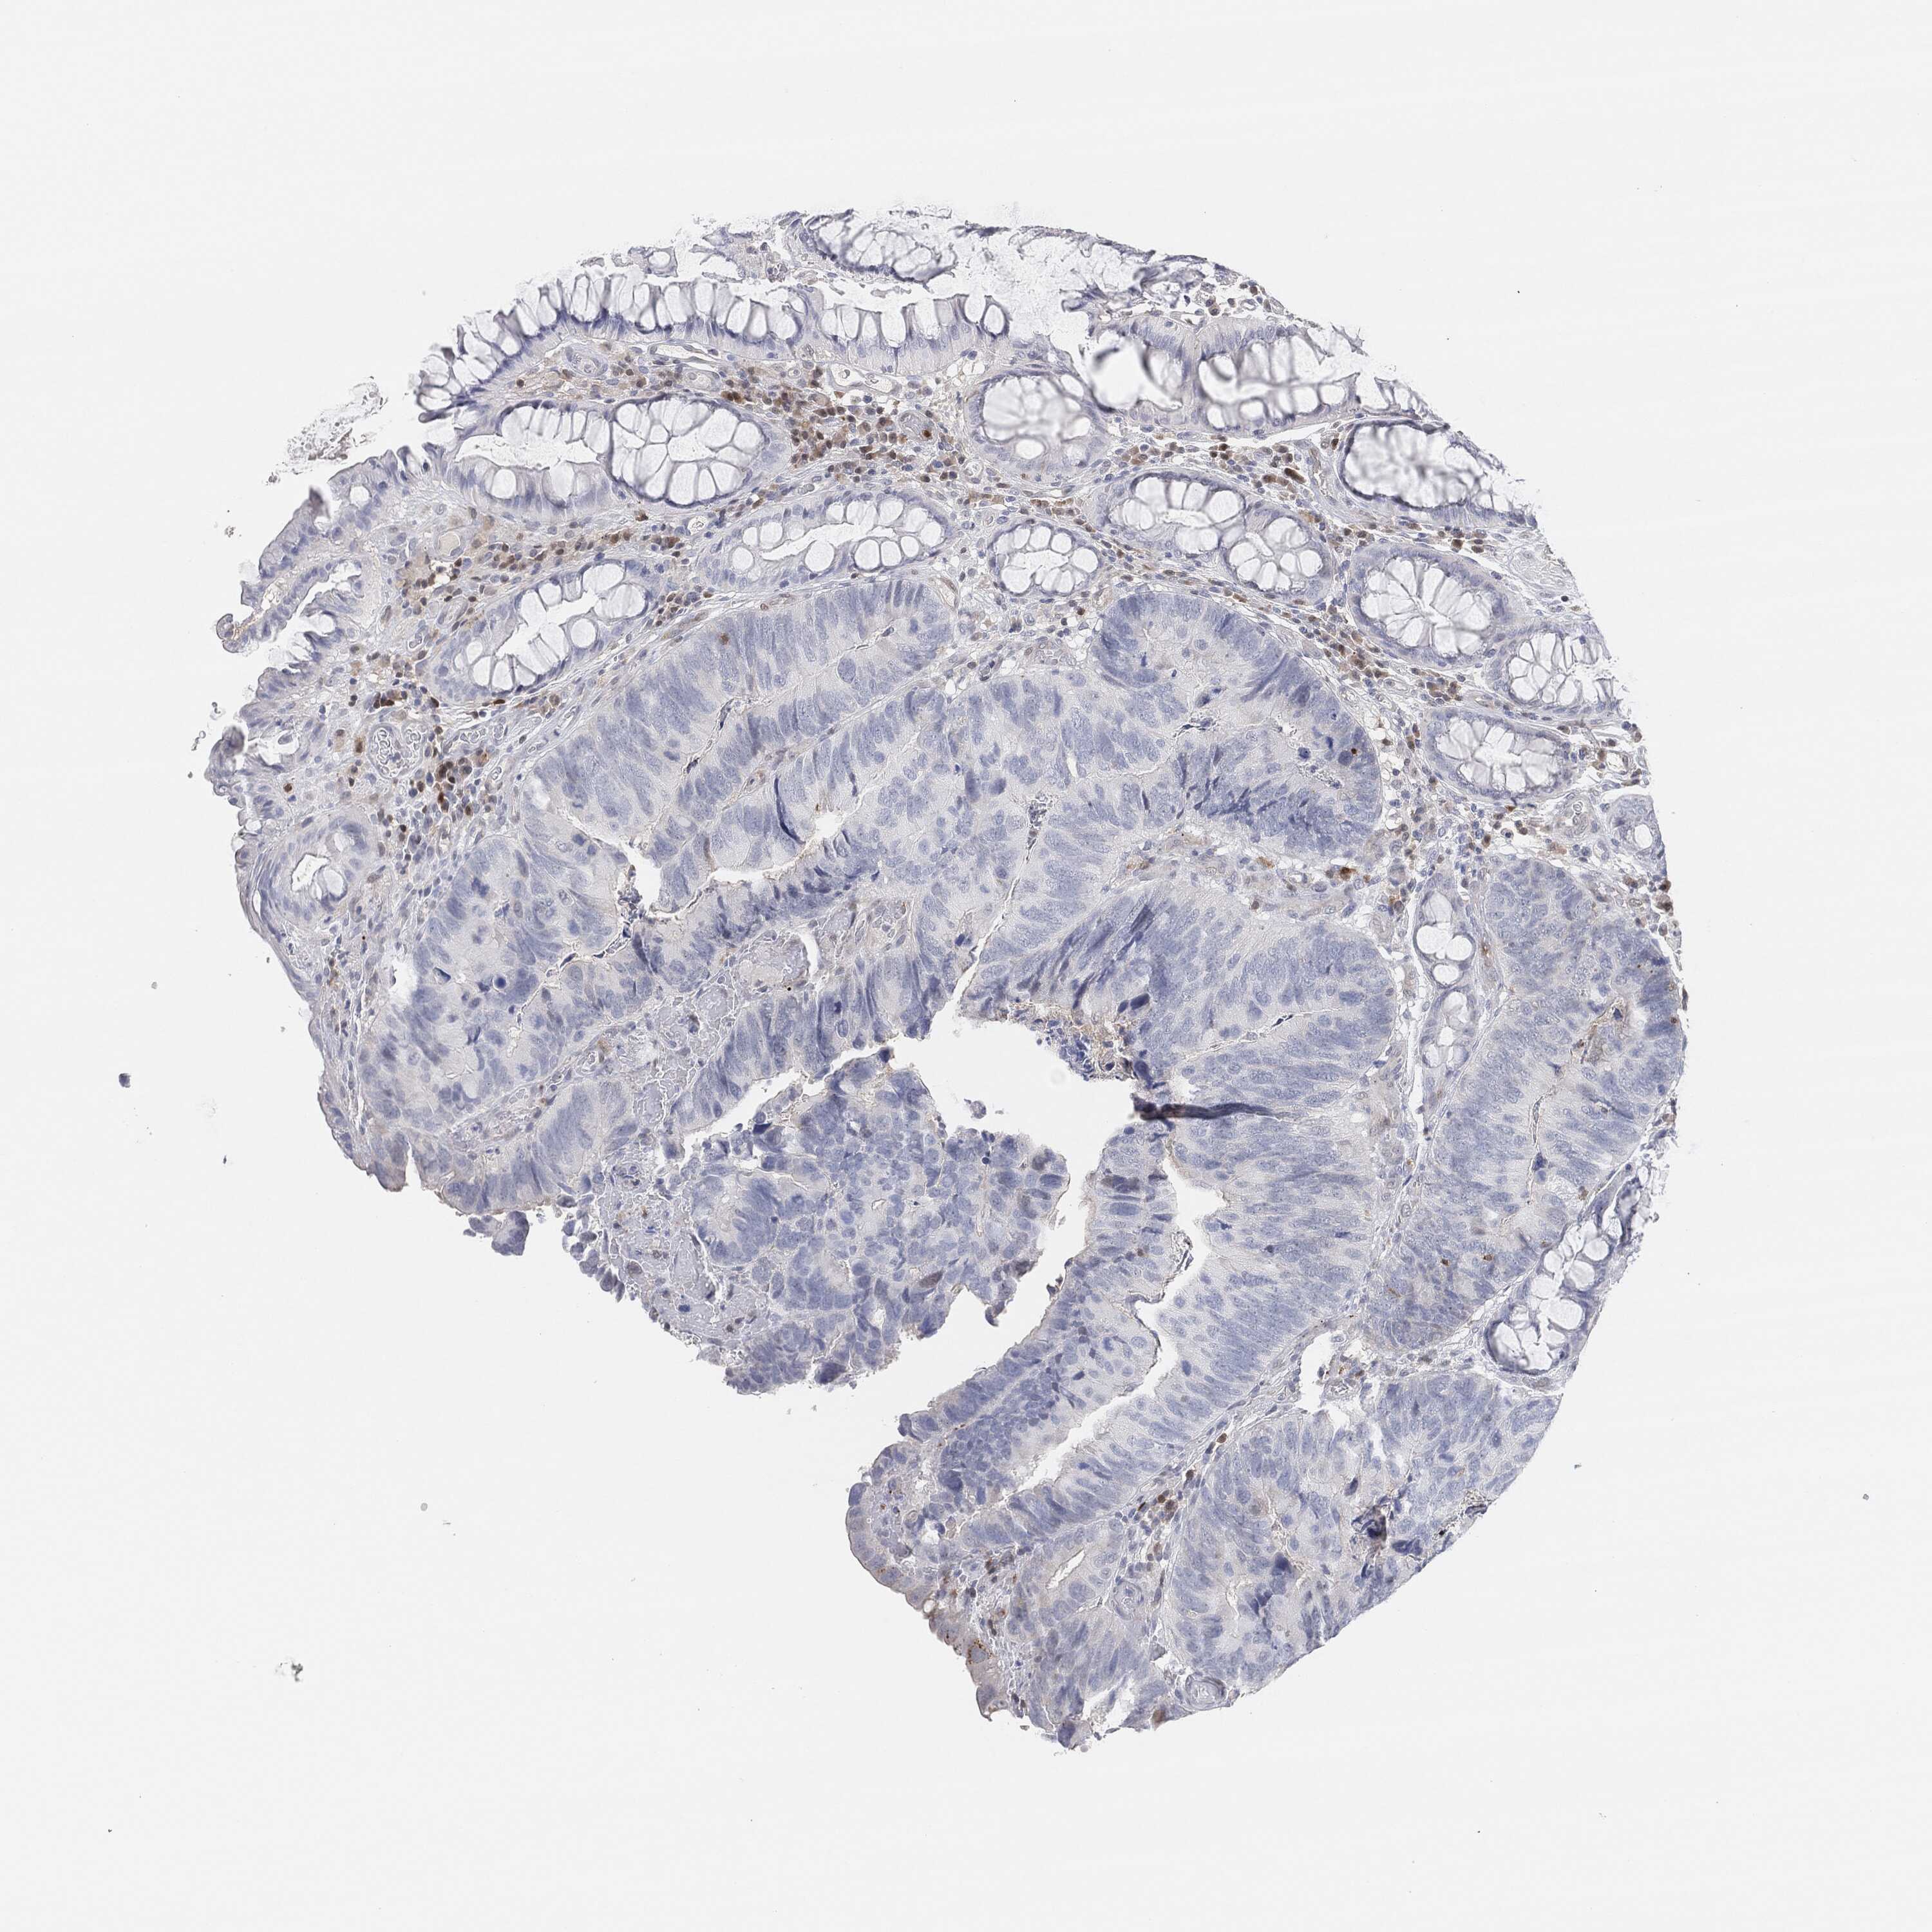

Colorectal cancer

Human cancer

Colon adenocarcinoma